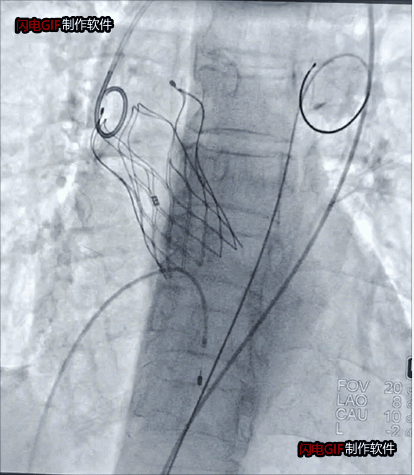

瓣狹窄患者瓣膜植入后影像

為避免激素可能對(duì)血管帶來(lái)的影響及血管入路并發(fā)癥,術(shù)前,徐州市一院心臟瓣膜病團(tuán)隊(duì)通過(guò)全面評(píng)估和檢測(cè),為其設(shè)計(jì)了充分的應(yīng)對(duì)方案。術(shù)中,麻醉科副主任王德領(lǐng)、醫(yī)師趙盼盼克服了血壓極度波動(dòng),循環(huán)衰竭、崩潰等潛在風(fēng)險(xiǎn),為手術(shù)的順利開(kāi)展鋪平道路。趙躍武在超聲科主任陳炳華、心胸外科副主任醫(yī)師嚴(yán)文俊、導(dǎo)管室護(hù)士長(zhǎng)孫寧帶領(lǐng)的護(hù)理和技師團(tuán)隊(duì)的通力配合下,經(jīng)反復(fù)確認(rèn)入路血管彈性和脆性后,經(jīng)左側(cè)股動(dòng)脈切開(kāi),手術(shù)圓滿(mǎn)完成。

國(guó)家心血管病中心心臟內(nèi)科學(xué)主任吳永健為本次手術(shù)提供了遠(yuǎn)程指導(dǎo)。本次手術(shù)還邀請(qǐng)了徐州醫(yī)科大學(xué)附屬醫(yī)院心血管內(nèi)科主任醫(yī)師王誠(chéng)和醫(yī)師程守全的合作,體現(xiàn)了徐州本地醫(yī)者的團(tuán)結(jié)協(xié)作和無(wú)私無(wú)畏。